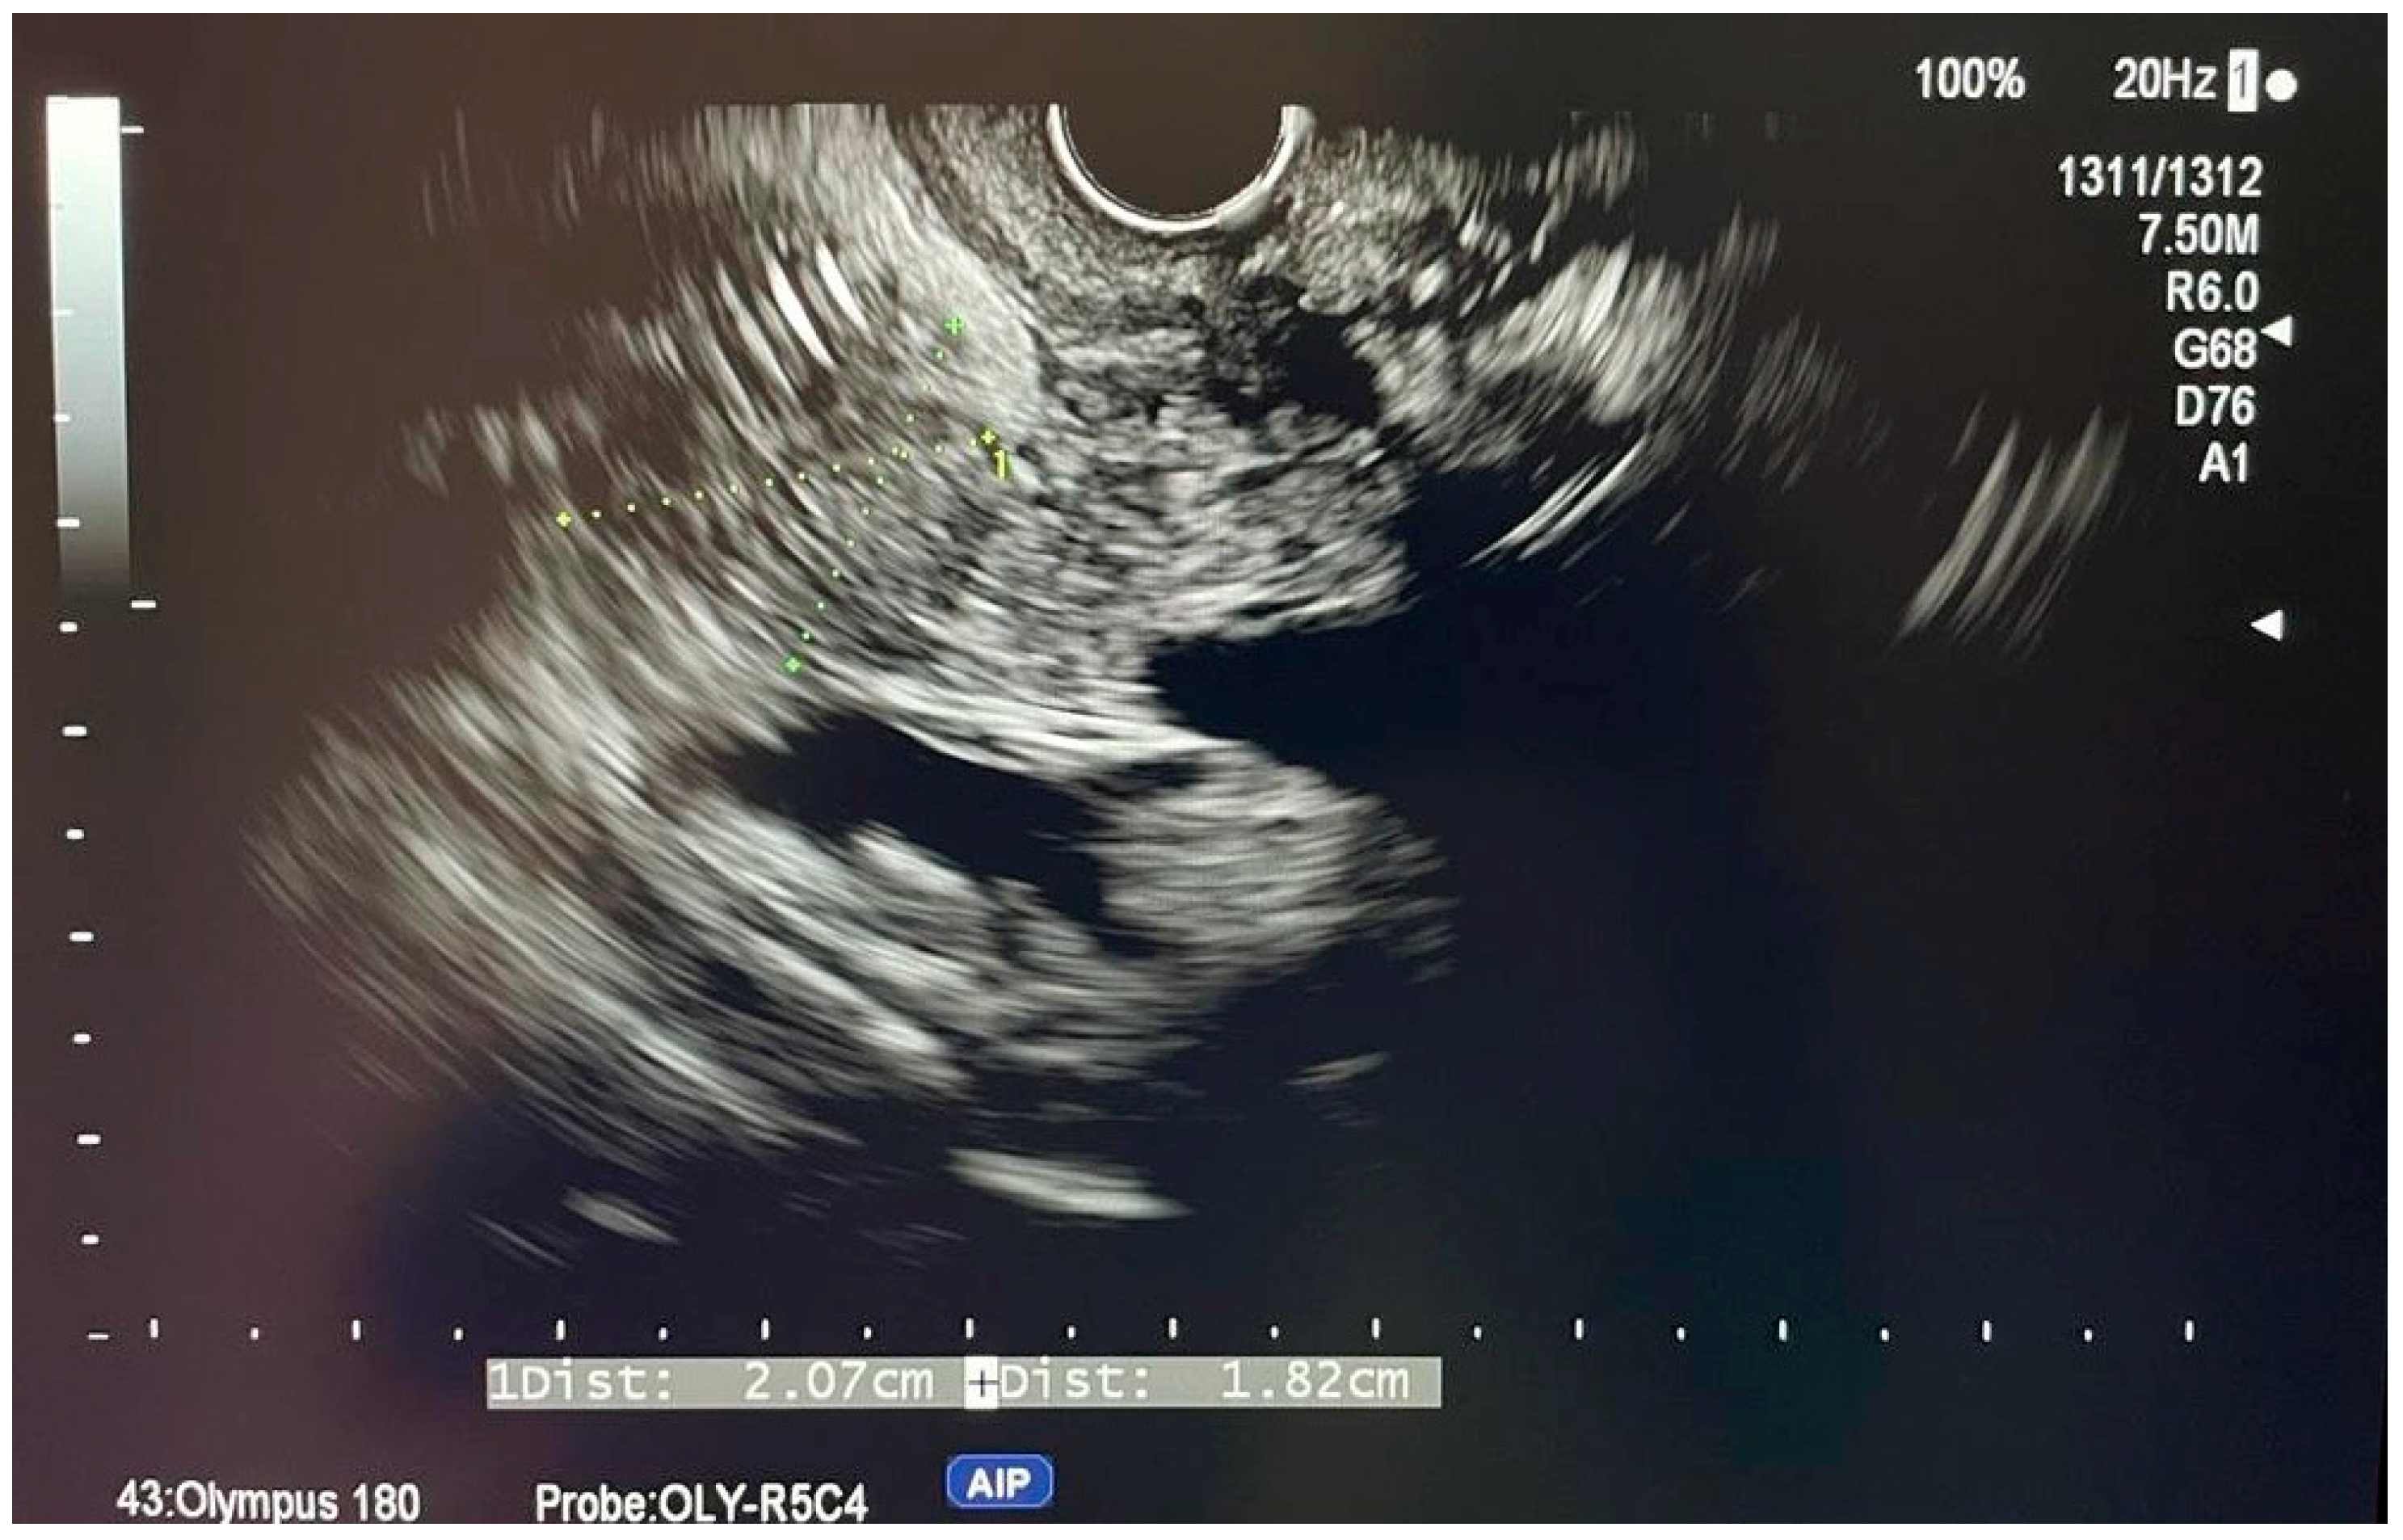

6.4.1. Endoscopic Ultrasound (EUS)

- Otsuka, Y.; Kamata, K.; Hyodo, T.; Chikugo, T.; Hara, A.; Tanaka, H.; Yoshikawa, T.; Ishikawa, R.; Okamoto, A.; Yamazaki, T.; et al. Utility of contrast-enhanced harmonic endoscopic ultrasonography for T-staging of patients with extrahepatic bile duct cancer. Surg. Endosc. 2022, 36, 3254–3260. [Google Scholar] [CrossRef] [PubMed]